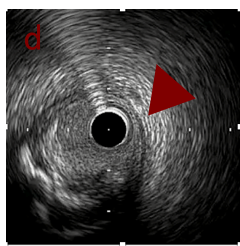

IVUS imaging after low speed 3回

OAS low speedによる引きのsandingを3回行いIVUSを確認するとa-cでは心筋側側へのOASによる良好なbias変化と、それに伴いdの健常側への危険なbias変化を認めた。

そのためcでIVUSマーキングを行い、その点より引きで赤線のpinpoint OAS high speedを行い、dに関してはinjury回避のためにOASを当てない方針とした。